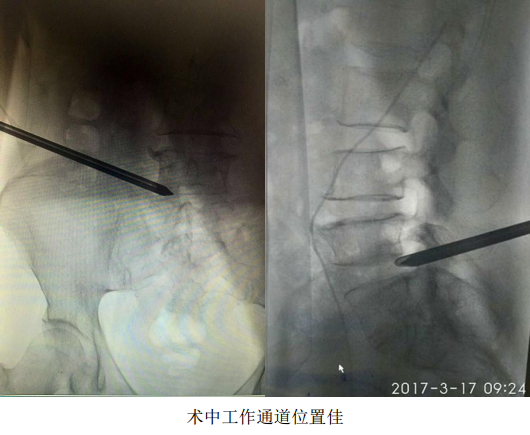

2017年3月17日,辽宁中医药大学附属医院骨伤二科,自主完成了院内首例治疗腰椎间盘突出症的椎间孔镜髓核摘除手术,开启了我院脊柱微创手术治疗的先河。此新技术的引进与开展,得到了院领导及医务处的大力支持,本次手术是由邓小磊医师在万贵良主任医师的协助下独立操作完成,受益者是一名患有腰5-骶1椎间盘突出症的57岁女性患者,此患者腰痛伴左下肢放射痛反复发作10年,复发10天,因疼痛无法下地活动行走,卧床10余天。术前经完善腰椎正侧位DR,腰椎CT和MRI等影像学检查,精准确定突出髓核的位置、性质及椎间孔骨质增生情况,详细规划手术策略,注重预判术中可能发生问题,提早制定解决方案。手术采取局部麻醉,切口约7mm,在DSA引导下,经椎间孔建立直径7mm的工作通道,使用椎间孔镜靶向摘除突岀的椎间盘髓核。手术医师在术中随时与患者语言交流,安全,顺畅。此例手术过程顺利,术后患者疼痛即刻缓解,并可下地行走。

脊柱内镜装置是由一个操作通道,一个光源通道和两个注水通道组成,术中操作时采用局部麻醉,经皮肤切一7mm大小的切口,在X线监视下,穿刺到突出的间盘,经过扩张通道后,椎间孔镜避开神经,进入病变部位,可视下摘除突出的间盘,达到治疗目的。脊柱内镜可根据术中需要,将图像放大30-50倍,可视下清晰靶向摘除突出的髓核,具有创口小,组织损伤少,安全性高,术后恢复快等特点,颠覆了传统的手术方式,此技术真正实现了腰椎间盘突出症的微创治疗,是快速康复理念的典型代表。